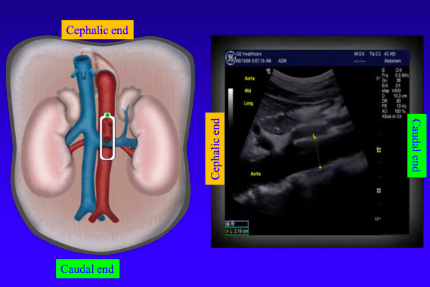

In \_________ view markers points to the patients head

longitudinal

When the ultrasound probe is sagittal (longitudinal) the top of the picture is _________

anterior

New cards

When the ultrasound probe is sagittal (longitudinal) the bottom of the picture is _________

posterior

When the ultrasound probe is sagittal (longitudinal) the left of the image is _________

cephalic (towards head)

When the ultrasound probe is sagittal(longitudinal) the right of the picture is _________

caudal (towards feet)

The probe marker is towards the patient's \__________ when the probe orientation is sagittal

head